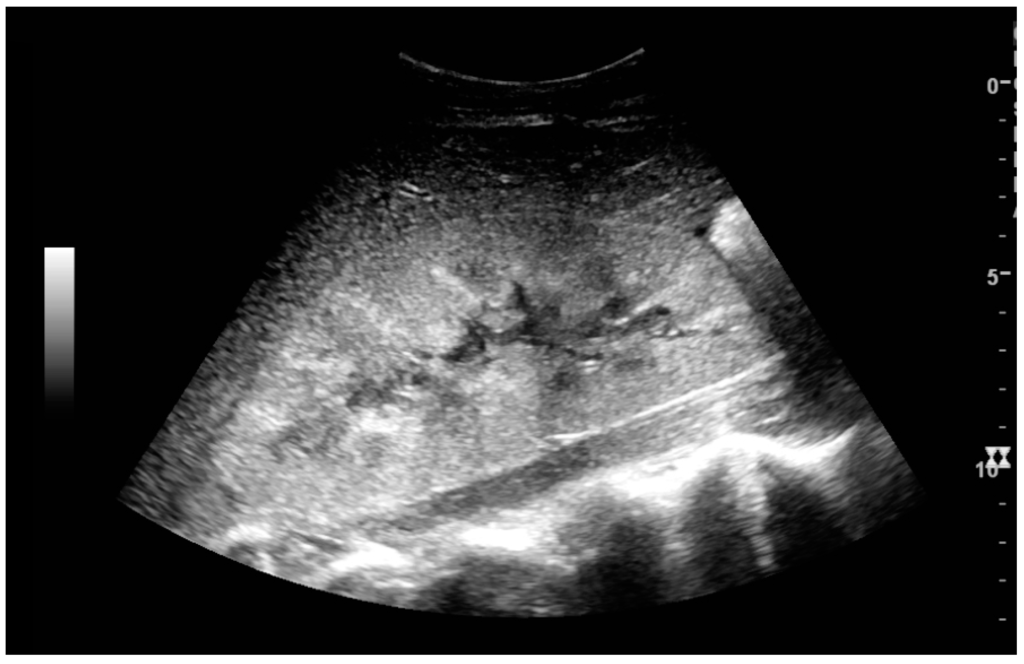

The acute changes in the kidney are often examined with US as the first-line modality, where CT and magnetic resonance imaging (MRI) are used for the follow-up examinations and when US fails to demonstrate abnormalities [31]. In evaluation of the acute changes in the kidney, the echogenicity of the renal structures, the delineation of the kidney, the renal vascularity, kidney size and focal abnormalities are observed (Figure 26 and Figure 27). CT is preferred in renal traumas, but US is used for follow-up, especially in the patients suspected for the formation of urinomas [32] (Figure 28).

Figure 28. Renal trauma with laceration of the lower pole and subcapsular fluid collection below the kidney.